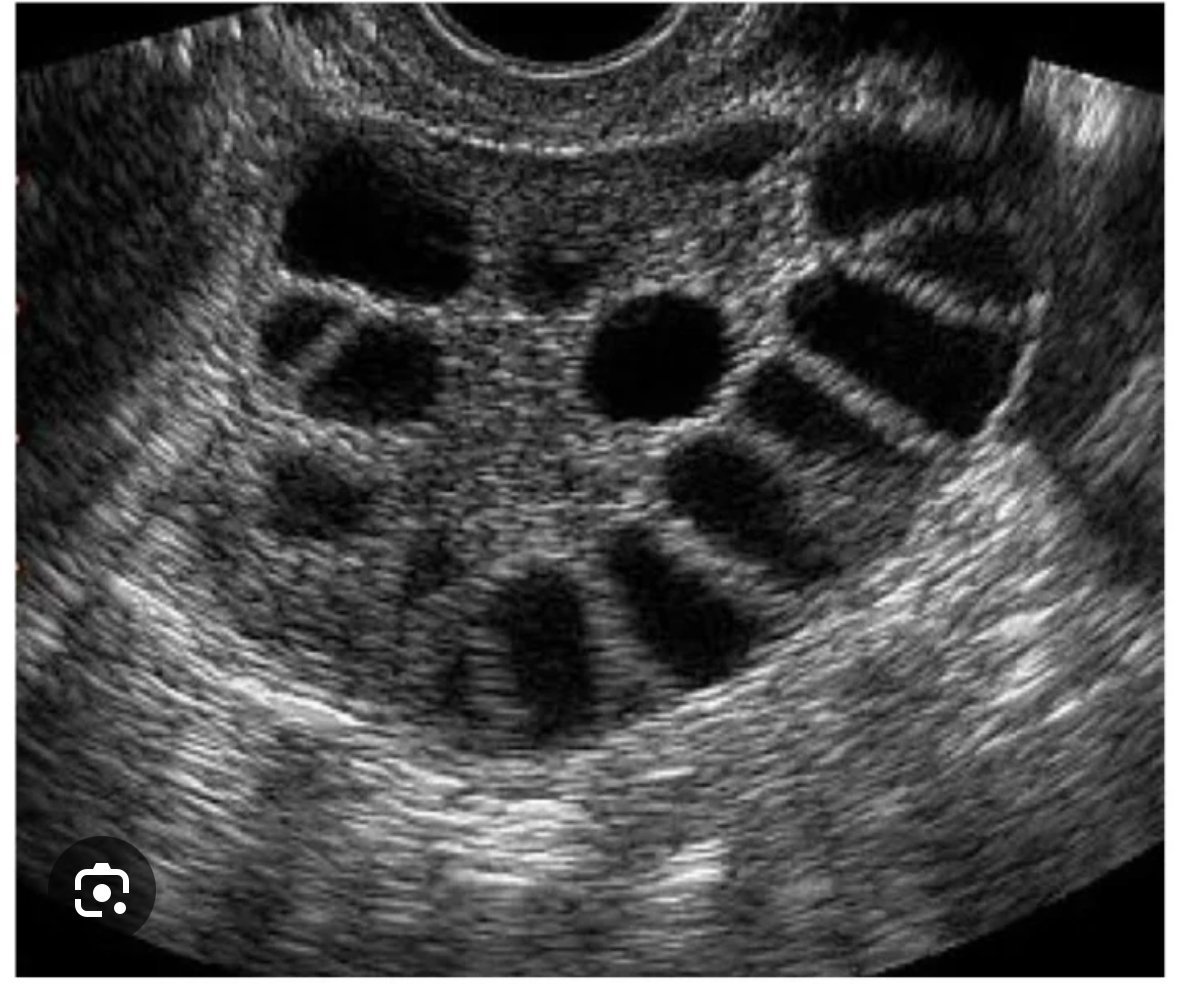

Believe23 поликистозата има доста проявления, като само едно от тях е високо АМХ, заради множество задържани фоликули. Нередовен цикъл, липса на цикъл, затлъстяване, инсулинова резистентност, окосмяване и разбъркани хормони. Обикновено FSH:LH е в полза на второто и е доста завишен. Ако имаш поликистоза, до сега док да ти беше казала. Ехографската находка е много типична, яйчника се вижда като “омотан” с гердан от маниста,

Консултирай се с док, нека те погледне на УЗД, пусни едни хормони на 2ри ден и ако всичко е наред, няма от какво да се притесняваш.